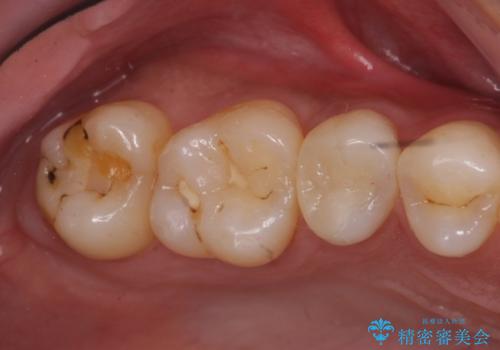

奥歯の虫歯 セラミックインレーに

- 上の奥の虫歯をセラミックインレーで修復しました。

奥歯は力がかかるところであるので、保険適応の白い材料は必ず劣化し、2次う蝕(再度虫歯)になる可能性が非常に高いですので全くおすすめできません。

2次う蝕になり、治療を繰り返していると抜髄(神経を取らないといけない)の可能性が高まります。